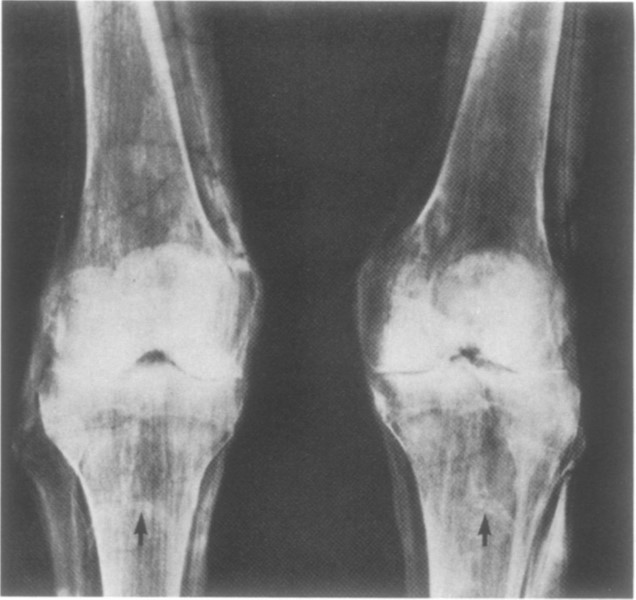

Mentre se sono coinvolti i vasi delle gambe (“dolore attraverso le cosce e le gambe tremano”) il papiro suggerisce una miscela di latte fresco, assenzio e natron, da far bollire e far bere al paziente sempre per quattro giorni. Da notare che secondo alcuni studiosi questo passaggio si riferirebbe alle vene varicose.